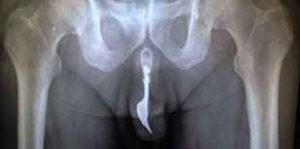

70歳のおじいちゃんがフォークをいれて抜けなくなってしまった!

なんてニュースが昔ありました。。。

【引用】imgassets.com